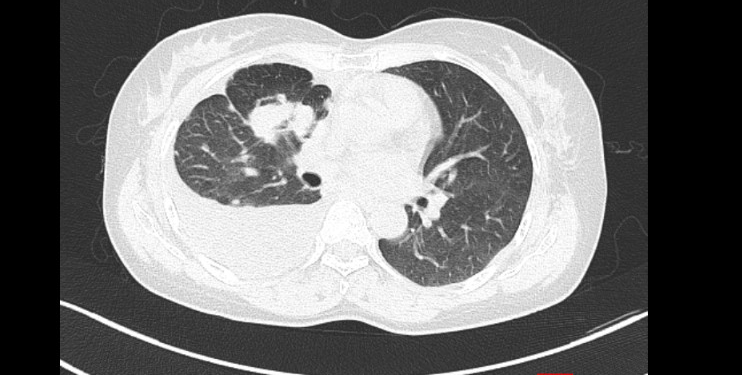

– Cắt lớp vi tính lồng ngực: U thuỳ trên phổi phải kích thước 25x41x70mm, xâm lấn rãnh liên thuỳ và màng phổi trung thất, nhiều nốt đặc nhu mô phổi 2 bên, hạch trung thất, hạch cổ phải, dịch màng phổi phải.

Hình 1: Hình ảnh chụp cắt lớp vi tính lồng ngực